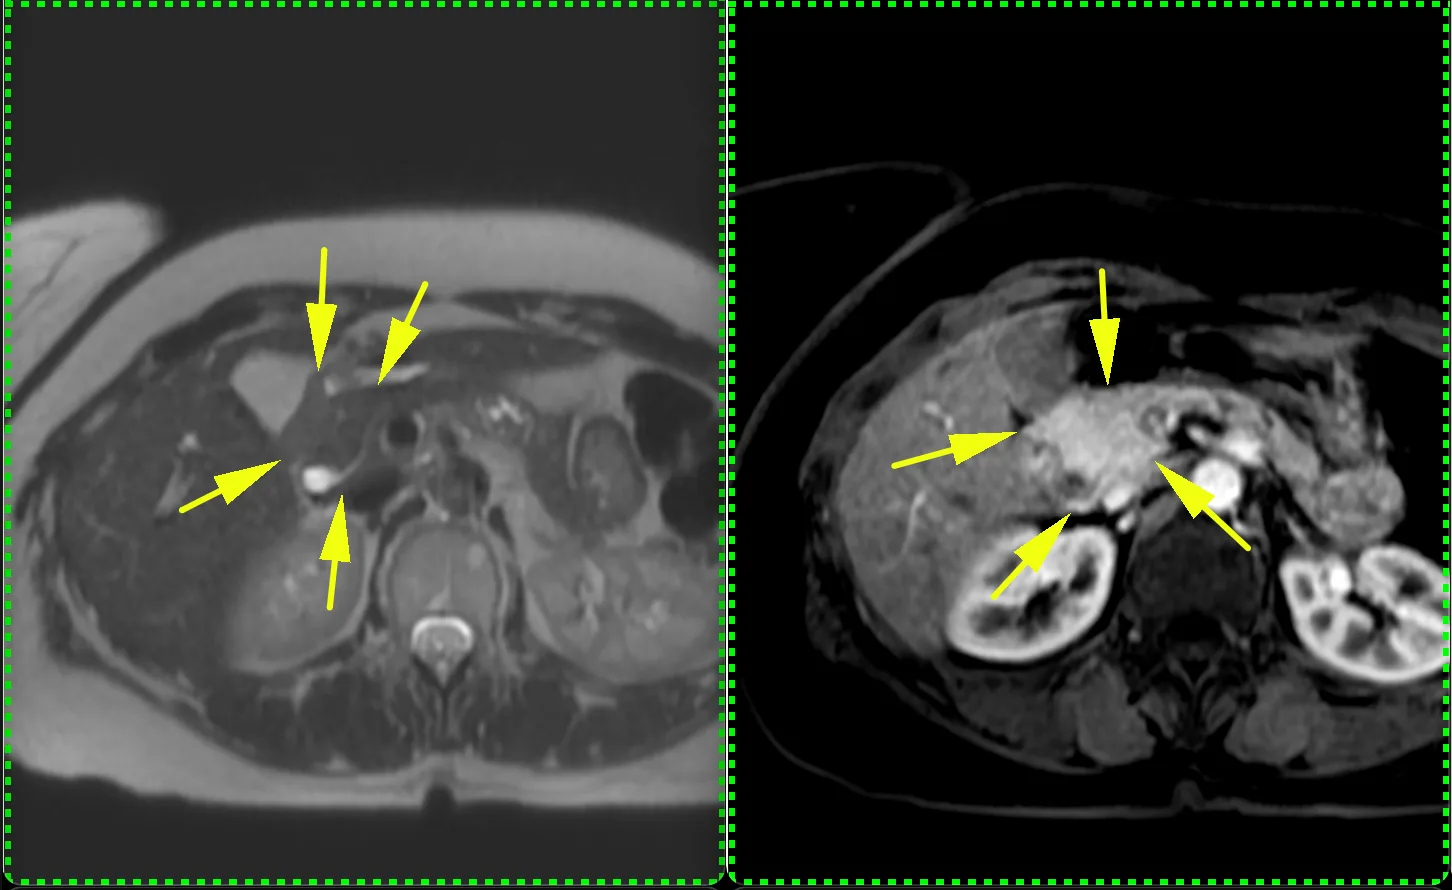

Хороший пример (не верифицирован, но все же, уж больно характерный вид) дифференциальной диагностики множественных новообразований печени. Пациент 63 года. Морфология кольцевидная и на контрастом усиленных сканах, и на диффузии, но не идеально шаровидная, солидный край толстый и неравномерной толщины, артериального гиперконтрастирования больше, чем у паренхимы печени нет (что против гепатоцеллюллярного рака), вымывания нет (тоже против ГЦР), накопление в центре постепенное и медленное. Голосую за периферическую холангиокарциному (или первично множественную, или с внутрипечёночной диссеминацией). А ещё за холангиокарциному - ретракция контура печени и расширение протоков мелких вверх по течению: это достаточно специфично именно для холангиокарциномы. Для гиперваскулярных метастазов нехарактерно отсутствие гиперваскулярности (нет быстрого накопления с вымыванием), на гиповаскулярные, в принципе, паттерн контрастирования, похож, но не похожа морфология (не шарики, не идеальные колечки, ретракция печени, расширение протоков вверх по течению - не характерны для метастазов). Посмотрим, угадаем ли. Но случай интересный. Показательный.